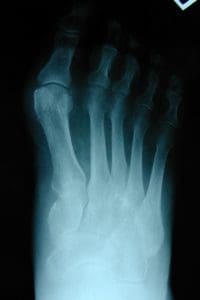

A bunion (hallux valgus) occurs when the big toe angles inward toward the second toe. This shift causes the joint at the base of the big toe to protrude outward, creating a visible bump. Over time, the deformity can worsen, leading to increased pain, difficulty fitting shoes, and changes in how you walk.

X‑rays to evaluate joint angles and arthritis